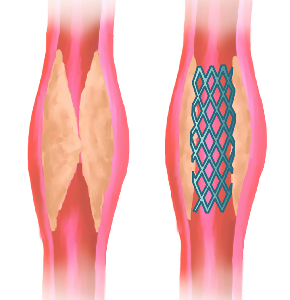

Detailreiche Fotografien aus der medizinischen Praxis ergänzen die Texte; moderne, genaue,

wissenschaftliche Zeichnungen geben Einblick in die Anatomie und die Funktion der Lunge und

anderer Organe.